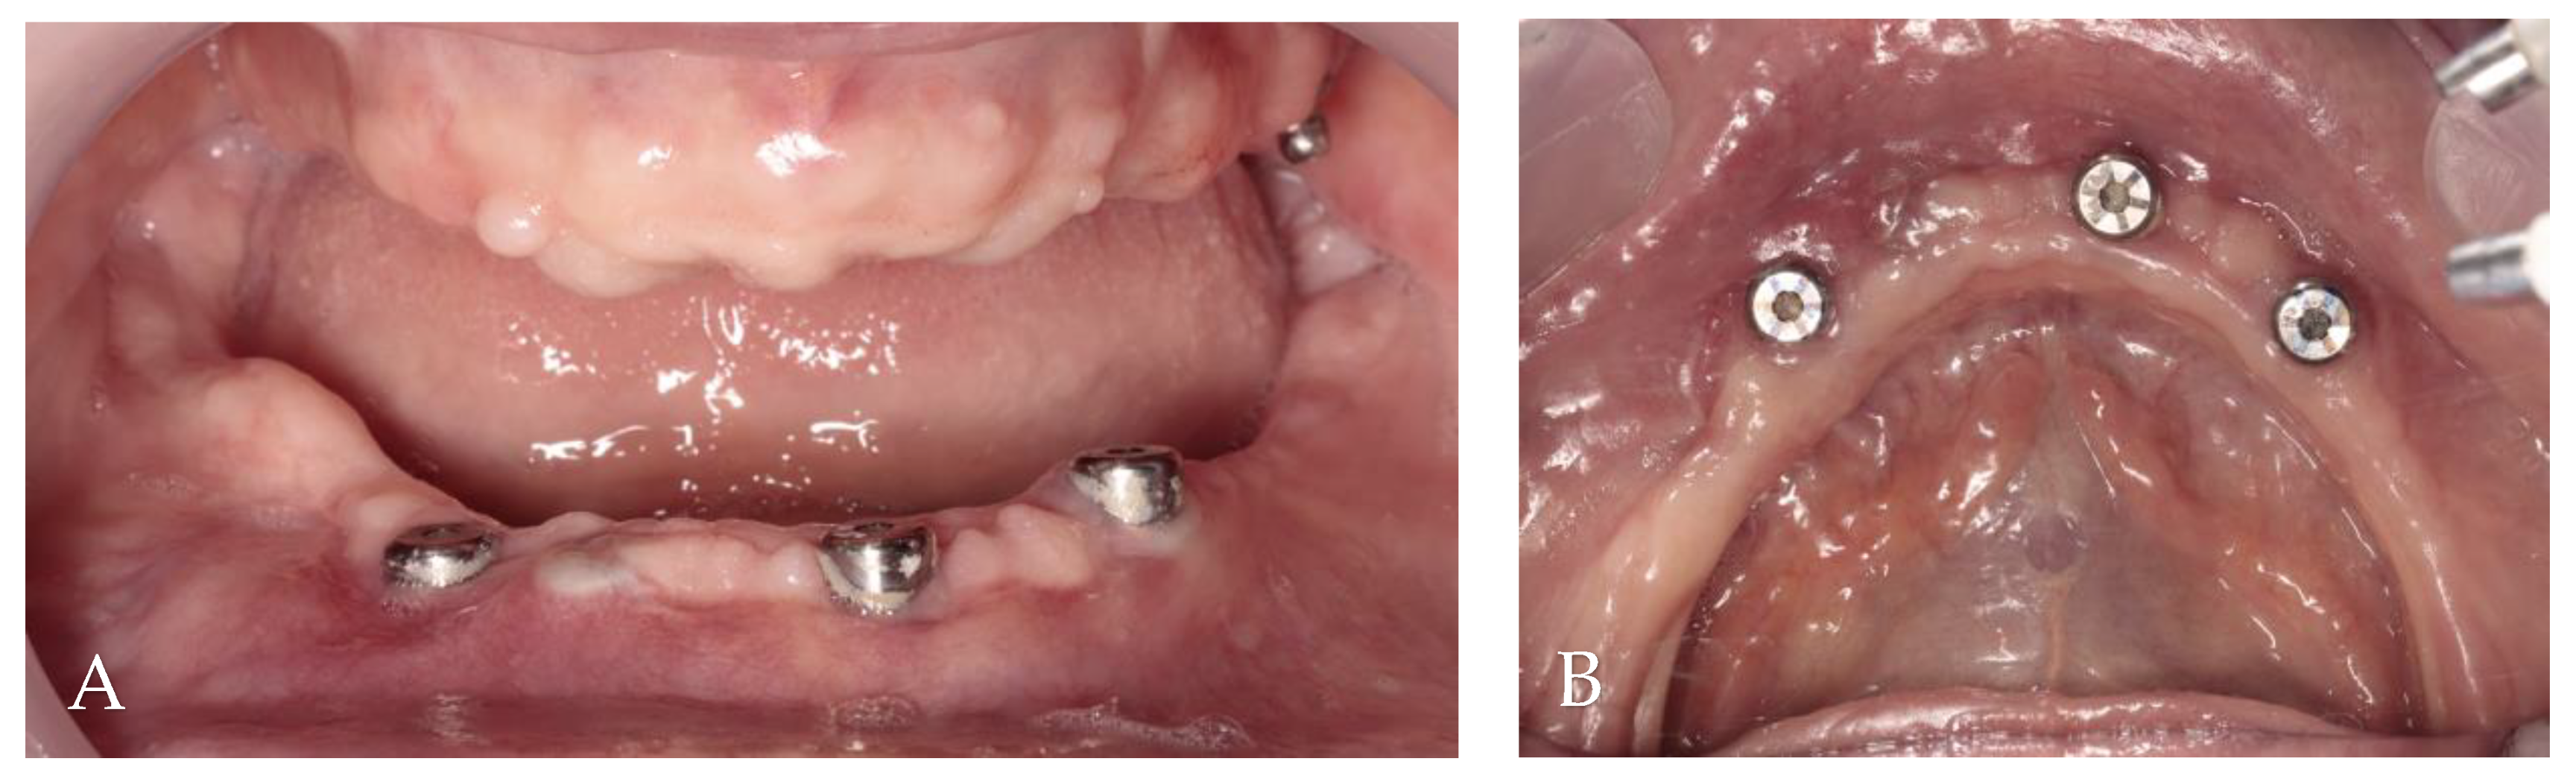

3.3. Surgery 2—Apically Positioned Partial-Thickness Flap (APPTF) in Combination with Free Gingival Grafts (FGGs)

3.4. Results